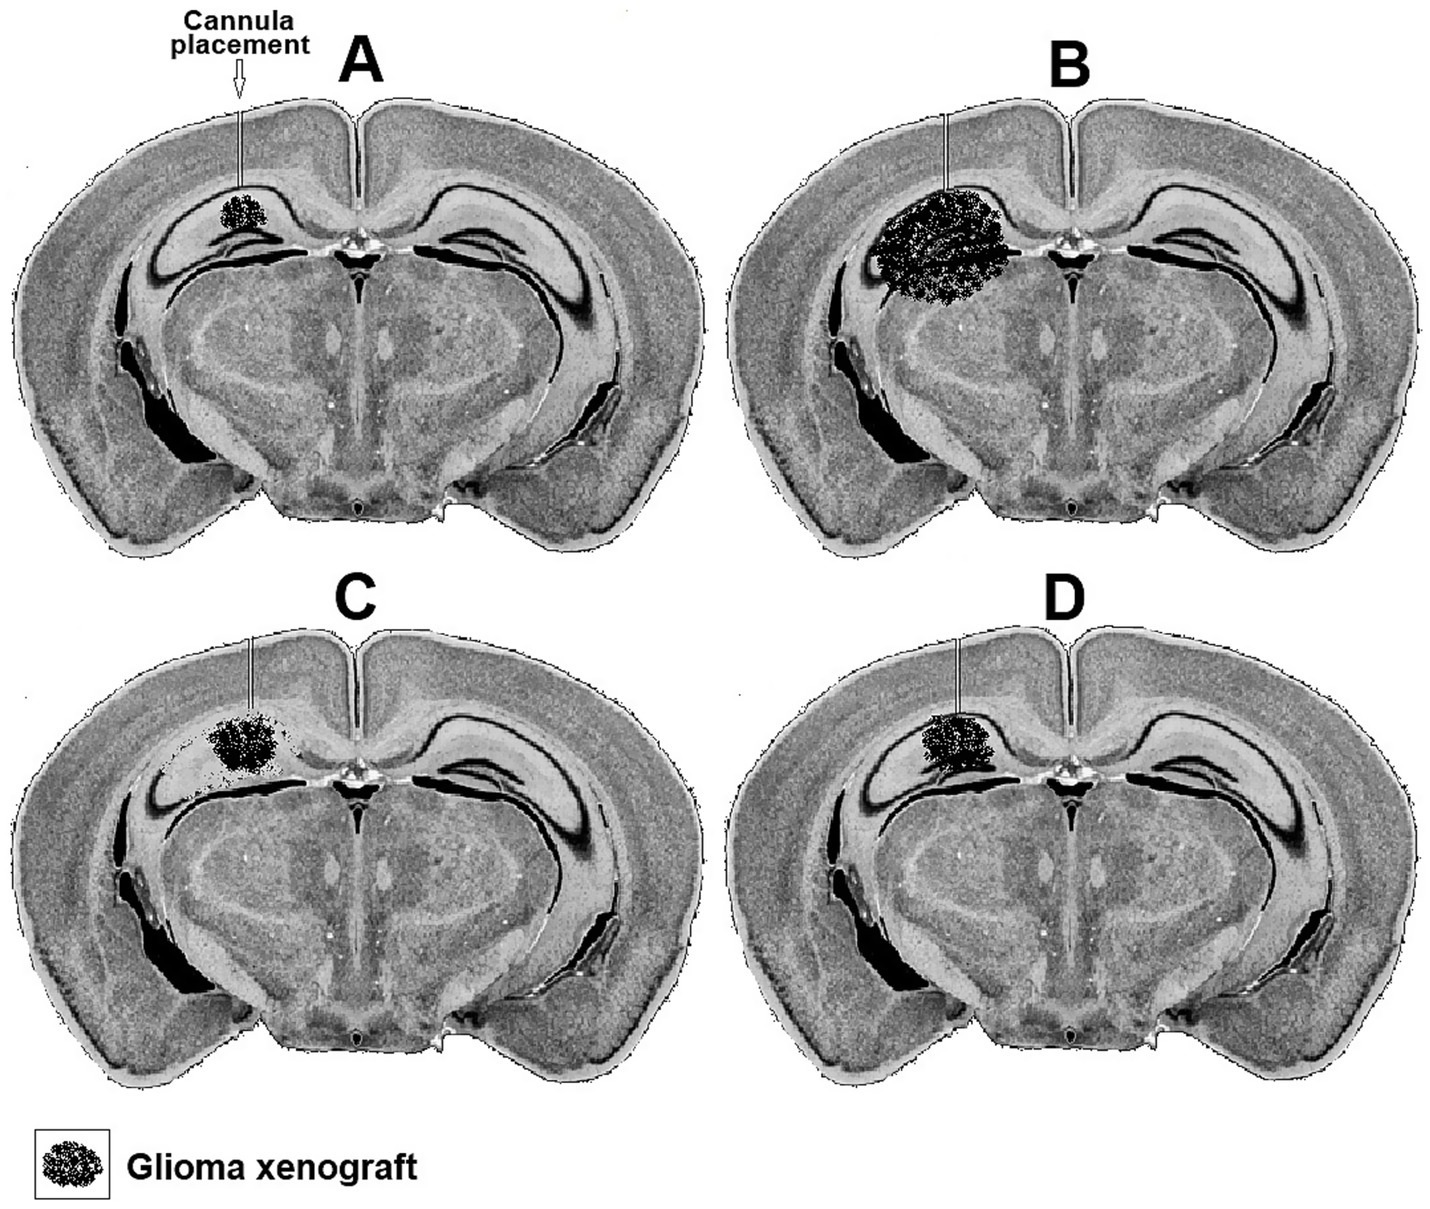

Both the short-term effects of such treatments on the levels of glucose and lactate at the interaction region of the xenograft with the hosting neuronal tissue can be measured along with their long-term effects on the rate of the xenograft proliferation. Figure 3 postulates how photomicrographs of coronal sections prepared from mice inoculated in their hippocampus with rat glioma xenograft would appear following different treatments. The progression of the glioma xenograft proliferation from 7 days (Figure 3A) to 14 days post inoculation (Figure 3B) is indicated by the enlargement of the tumor in B compared to A. Placement of a cannula in the hippocampus near the xenograft allows the delivery of chemical agents. In the example shown, the glial TCA cycle inhibitor FC was delivered daily starting on day eight after inoculation (Figure 3C) slowed down the glioma proliferation, but also damaged many pyramidal neurons in the hippocampus, since the FC is also toxic to astrocytes, the suppliers of lactate to neurons. If, however, FC was delivered along with lactate, the glioma proliferation slowed down without damaging the pyramidal neurons (Figure 3D).

Figure 3. Representative hypothetical photomicrographs of brain coronal sections taken from four groups (A–D) of mice showing a xenograft of rat glioma a week (A) and 2 weeks after inoculation (B). A cannula implanted close to the xenograft in the hippocampus used to deliver daily buffered solutions (vehicle) to A and B or buffered solutions containing FC (C) or FC + lactate (D) starting on day eight.